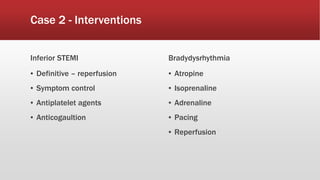

This document discusses various cases of collapse and syncope. It defines collapse as transient loss of consciousness with loss of postural tone and full recovery. Syncope is defined as loss of postural tone with or without loss of consciousness and full recovery. It then discusses the multiple potential causes of collapse and syncope including toxicological, cardiac conduction abnormalities, structural cardiac issues, autonomic dysfunction and more. It then goes through 9 case examples, discussing important questions to ask, potential tests and interventions for each case.